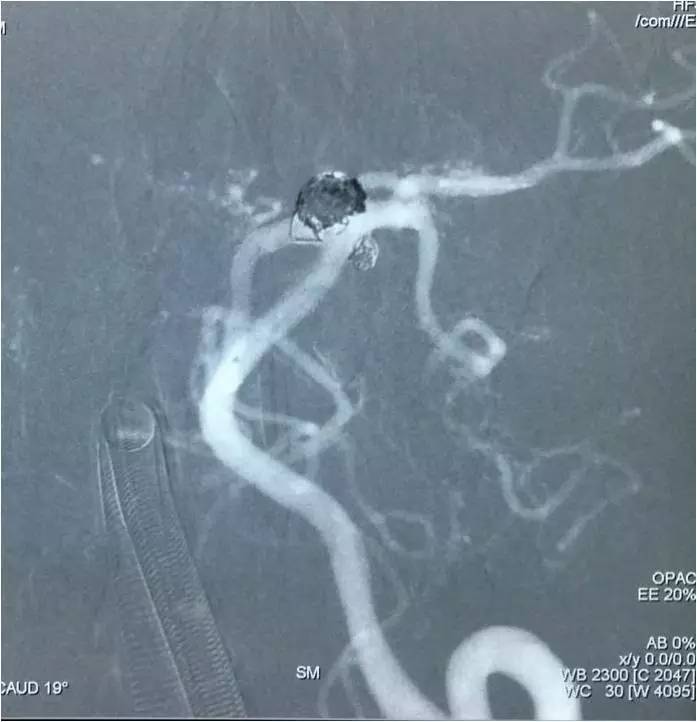

▼Headway17完成左小脑上动脉瘤的栓塞后,再经支架网眼导入右PCA,将第二枚LVIS JR 3.5*23支架跨瘤颈释放入右PCA-基底动脉,如此完成了Y型支架的释放,为基底动脉顶端动脉瘤的栓塞工程摆好了脚手架。

▼微导丝经支架内部弓背进入右PCA,Headway17微导管跟进,目的是加强第二枚支架(穿过了第一枚支架的网眼)的扩张性和贴壁性。

▼在Y型支架保护下经预置于瘤腔内的Echelon10微导管栓塞基底动脉顶端动脉瘤。

▼依次填圈,由于管头是朝向瘤腔右侧的,所以弹簧圈主要聚积在瘤腔右侧。

▼瘤腔左侧部还有空虚。